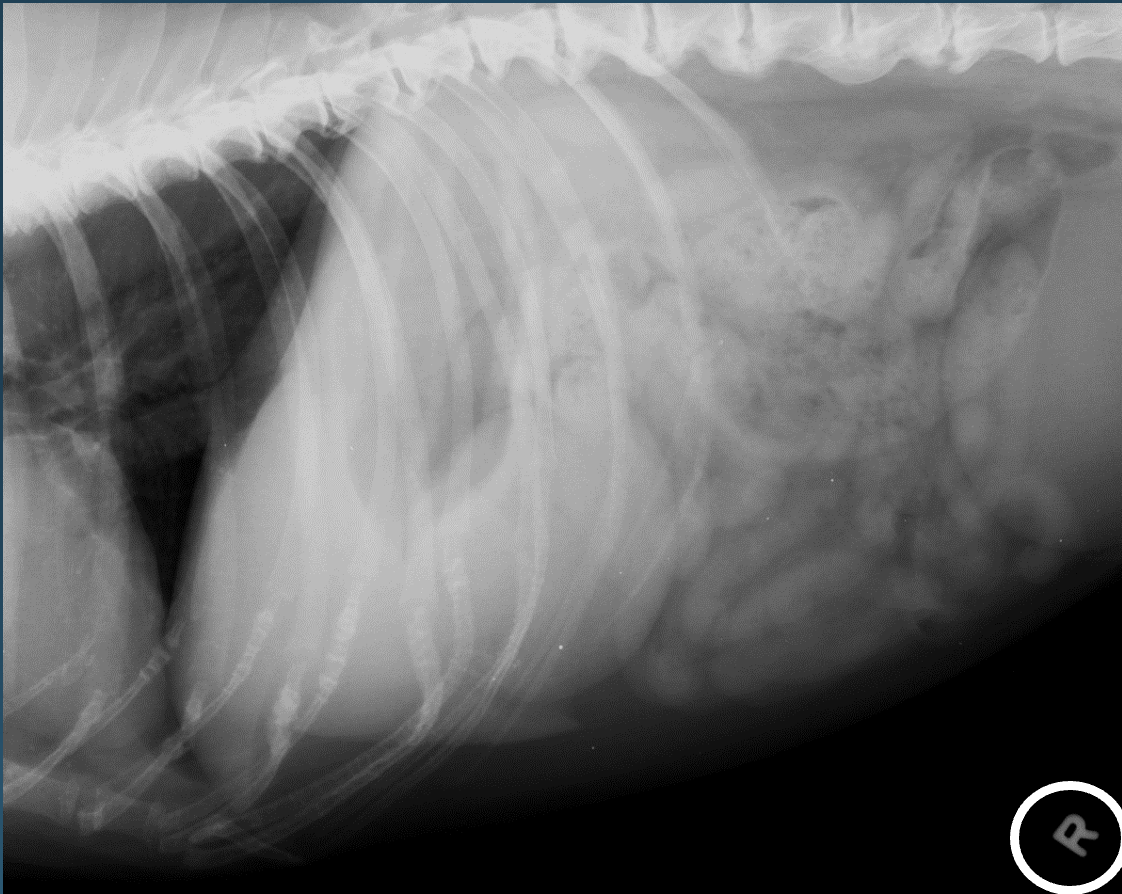

What is shown in these images?

normal upper GI contrast study in a dog